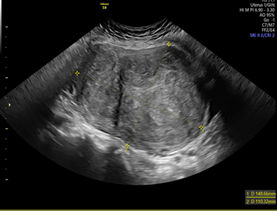

In the anatomopathological study, the macroscopic aspect of the uterus was normal (Figure 3), with several subserous nodular structures, the largest of 11 cm in diameter, whitish and fasciculated in appearance, of elastic consistency with focal yellowish areas compatible with uterine myoma.

Figure 3 Myomatous uterus, subserosal myoma of 11 cm in greatest

diameter.Myomatous uterus, subserosal myoma of 11 cm in greatest diameter.